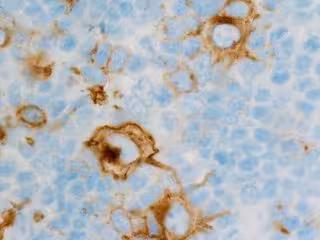

Archivo - Linfoma

Archivo - Linfoma - FLIKR/CNICHOLSONPATH - Archivo

En el ensayo se probó la eficacia de Loncastuximab tesirina, un complejo de anticuerpos y fármacos dirigido a CD19, la misma molécula a la que se dirige la terapia CAR-T en las células B del linfoma. El complejo farmacológico se adhiere a la CD19, ampliamente expresada en las células B del linfoma, y hace llegar la carga del fármaco al interior de la célula, minimizando así la toxicidad sistémica. Una vez internalizado, el fármaco daña el ADN de las células del linfoma, provocando su muerte.